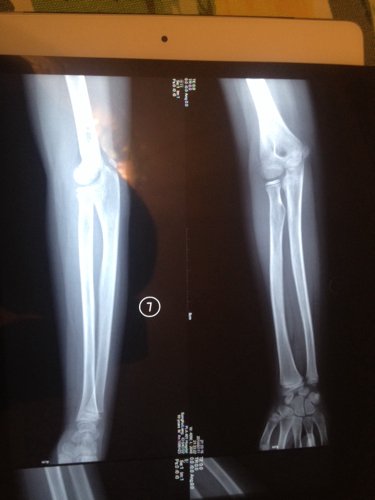

右肘玩的时候摔着了,三个蒙古的医生也没说明白是怎么回事 现在在转胳膊就痛 10岁的小孩 点击展开 匿名用户 2014-07-11 23:14 为您推荐: 其他回答 你好哦,你给宝宝做康复了吗,一般这时候是需要去做一下康复的呢,这样是会更好一些的啊 可靠的悠闲80 2014-07-12 17:41 相关问题 小孩6个多月,抱小孩时胳膊响了一下,孩子就哭个不停,响的那个胳膊就一直不动,请问医生是不是脱臼了 怎么感觉第二张图片上面,那个小孩的胳膊上面怎么好像长了个手指啊,当时检查的时候医生没说什么,今天回 请怎医生我家小孩胳膊上怎么会农了